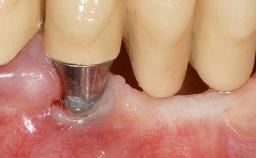

Early Implant Placement, Contour Augmentation, and Autologous Connective-Tissue Graft Using a Tunneling Technique to Replace an Upper Incisor with Generalized Gingival Recession

| # of Implants | 1 |

| Attachment | Reduced-Diameter|Two-Piece |

| Bone Augmentation | Horizontal|Simultaneous |

| Soft Tissue Grafting | Simultaneous |